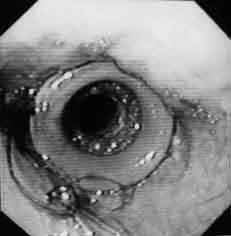

Este posibil să se utilizeze două metode de introducere a endoprotezei în esofag. La primul - fibroendoscopul este efectuat sub zona leziunilor tumorale. Apoi, ghid de coarde fiberscope canal instrumental este avansat, astfel încât sa vârful atraumatic liber situat fie în stomac antral (tumora esofagiana) sau în lumenul intestinal (tumori esofagiene la anastomoză recidiva). Extracția treptată a endoscopului este însoțită de umflarea șnurului la adâncimea corespunzătoare. Apoi, șirul pe Bugey endoproteza introdus printr-un tub de împingere, suprafața exterioară care se aplică o etichetă care corespunde unei distanțe de limita superioară a îngustării marginile frontale ale dinților. După proteza din BOUGIE esofag la adâncimea dorită cu șirul este îndepărtat, iar prin lumenul fibrobronhoscopie tubului împingându administrat pentru a controla poziția endoproteza (fig. 1). Dacă este nevoie, atunci sub control endoscopic vizual, endoproteza poate fi deplasată mai jos cu un tub de împingere.

Fig. 1. Endofotografia marginii superioare a endoprotezei esofagului